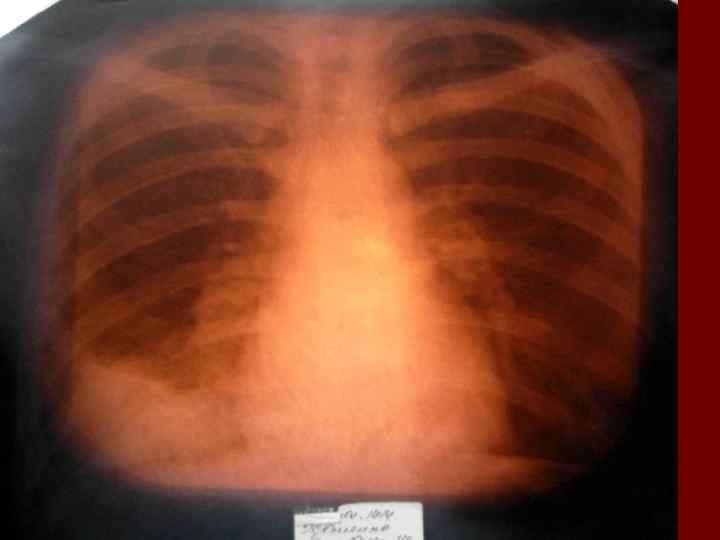

Долевая пневмония характеризуется лобарным пневмоническим инфильтратом. Крупозная ( пневмококковая) пневмония диагностируется прежде всего по клиническим данным. Крупозная пневмония сохраняет свою типичную картину пневмококковой пневмонии: острое начало с характерными клиническими данными, циклическое течение, несклонность к деструкции, гомогенной и лобарной инфильтративной тенью при рентгенологическом исследовании. Вместе с тем, широкое использование антибиотиков способствовало значительному снижению числа крупозных пневмоний у детей. Интерстициальная – редкая форма пневмоний, при которой оказывается поражен прежде всего интерстиций. Как правило, интерстициальная пневмония обусловлена вирусами, пневмоцистами, внутриклеточными микроорганизмами и грибами.

Морфологическую форму пневмонии определяют по клинико – рентгенологическим данным: выделяют очаговую, очагово – сливную, долевую ( крупозную), сегментарную и интерстициальную пневмонии. Очаговая – наиболее распространенная форма. Пневмонические очаги чаще бывают размером 1 см и более. Очагово – сливная – инфильтративные изменения в нескольких сегментах или во всей доле легкого, на фоне которых могут быть видны более плотные участки инфильтрации и/или полости деструкции. Сегментарная – в процесс вовлекается весь сегмент, который, как правило, находится в состоянии гиповентиляции, ателектаза. Морфологическая картина воспаления при очаговых и сегментарных пневмониях связана с первичным инфекционным воспалением в бронхах, что дает основание отнести эти варианты поражения легочной ткани к бронхопневмониям, нередко сопровождающихся бронхообструктивным или бронхообтурационным синдромами. В настоящее время данный тип пневмоний у детей встречается наиболее часто.